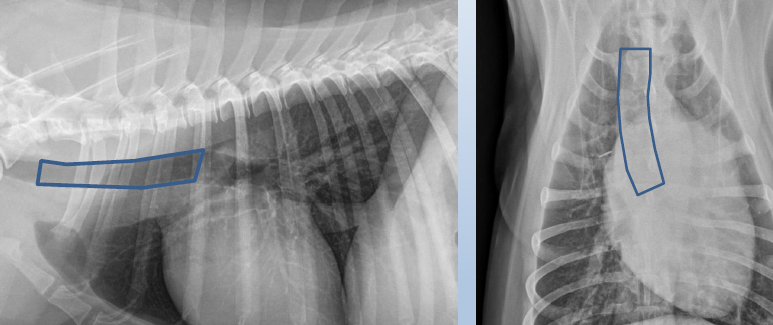

Lateral

Cardiac silhouette

Caudal mediastinal reflection

Caudal mediastinum

Caudal vena cava

Cranial mediastinum

Cranioventral mediastinal reflection

Descending aorta